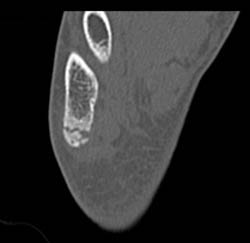

Vascular Mapping for Gluteal Flap Surgery